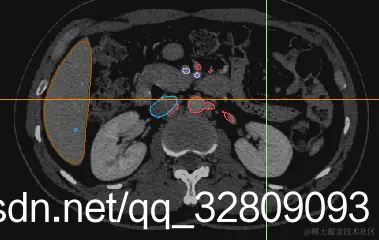

最后建模出来的效果:

正面图(肝脏+动脉+门静脉+腔静脉)                                反面图                                                          透视图

三种视图: